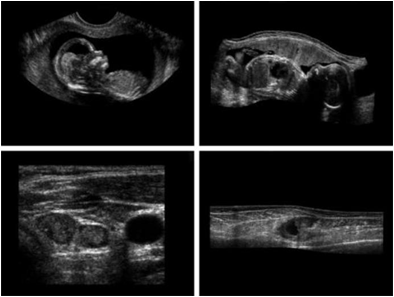

• 초음파: 1~5MHz 이하. 의료진단

Image

a)아기1 b)아기2 c)갑상선 d)손상된근육